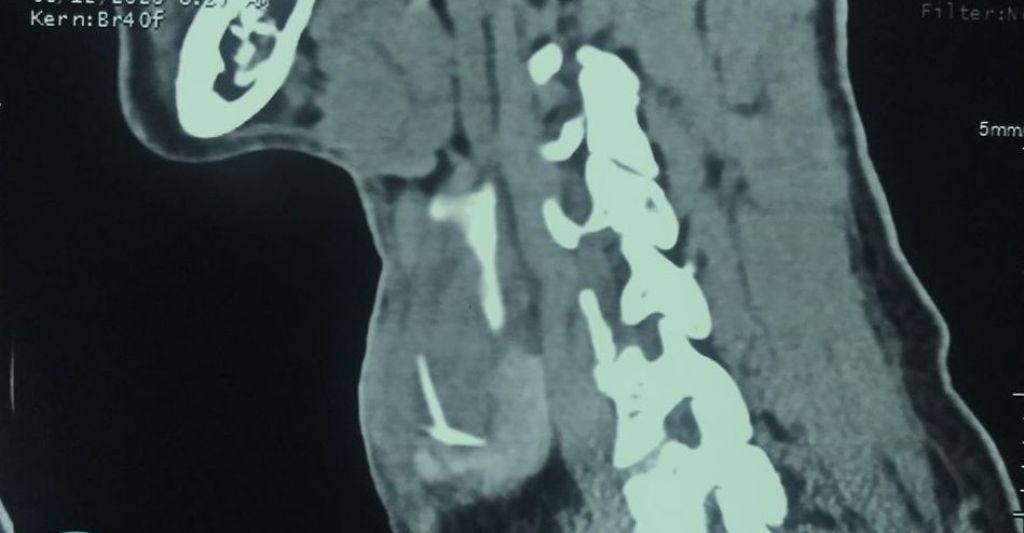

Bác sĩ khám nghĩ nhiều đến tình trạng áp xe vùng cổ trái. Bệnh nhân được chỉ định chụp CT-Scan vùng cổ. Kết quả phát hiện ổ áp xe tại thùy trái tuyến giáp, kích thước ổ áp xe khoảng 27mm, bên trong có dị vật nghi cản quang là xương cá khoảng 20mm có hình ảnh giống chữ T.

Suýt chết vì quên mình đã bị hóc xương cá từ... 4 tháng trước ảnh 1Hình chụp X-Quang bệnh nhân mắc xương cá (ảnh: BVCC)